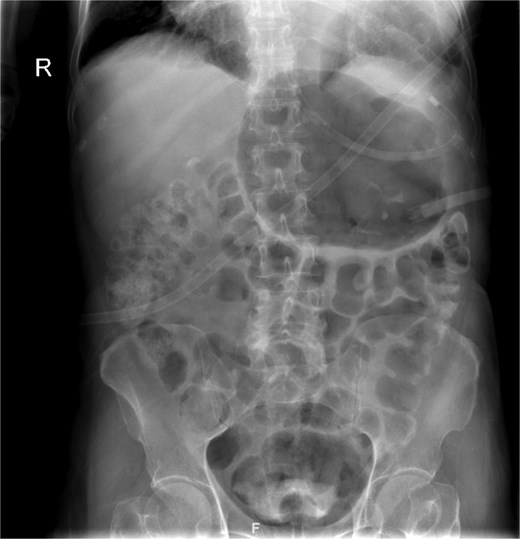

On presentation, the patient was fully oriented with vitals in the normal range. On examination, the abdomen was soft and not distended. There was a scar at the lower midline laparotomy for an unknown indication. There was no abdominal tenderness or any signs of peritonitis. All hernial orifices were intact. His laboratory results were unremarkable with a normal renal and electrolytes profile and no leukocytosis or anemia. Abdominal radiograph demonstrates multiple dilated loops of small bowel with prominent air-fluid levels. No evidence of free intraperitoneal air is identified to suggest perforation. No radiopaque foreign bodies or mass lesions are visible (Fig. 1). The patient underwent computed tomography (CT) of abdomen with IV contrast. The stomach demonstrates abnormal orientation with inferior displacement of the fundus and superior displacement of the gastric pylorus near the gastroesophageal junction, with gastric distension. Mild perigastric and perisplenic fluid. Preserved gastric wall enhancement. Mild pelvic fluid is noted (Fig. 2).

Contrast-enhanced CT abdomen and pelvis shows nasogastric (NG) tube noted in position. The stomach demonstrates abnormal orientation with inferior displacement of the fundus and superior displacement of the gastric pylorus near the gastroesophageal junction, with interval improvement of the gastric distension, likely mesenteroaxial gastric volvulus. Persistent mild perigastric and perisplenic fluid. Preserved gastric wall enhancement. Mild pelvic free fluid is noted. No free air or size significant lymph node.